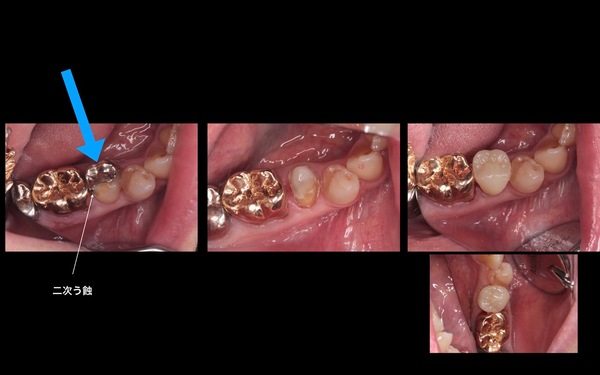

60代女性の奥歯の銀歯ブリッジ パラジウムブリッジ に発生した二次カリエスをジルコニアブリッジにて治療した例 赤坂の歯医者さん 赤坂クレール歯科クリニック